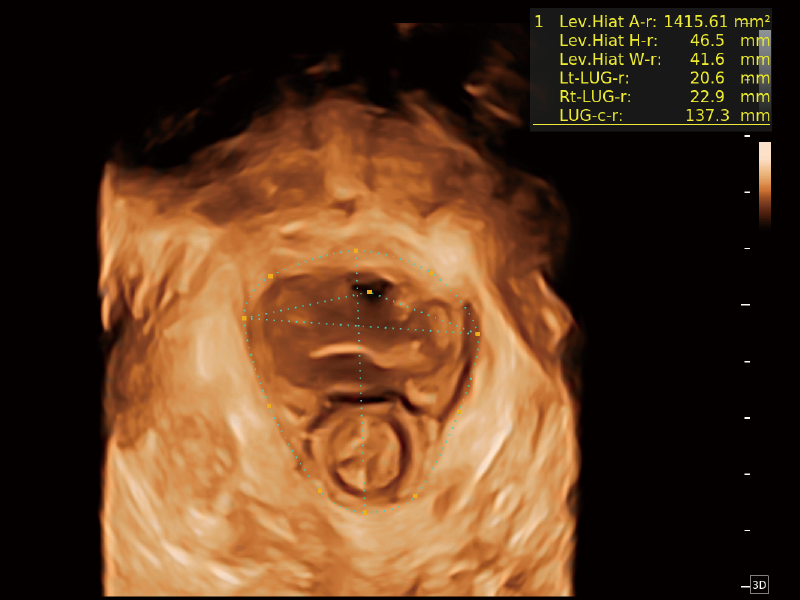

作為開(kāi)立醫(yī)療全新打造的超高端旗艦超聲產(chǎn)品,從探頭抬起喚醒開(kāi)啟掃查到多維探頭發(fā)射接收,通過(guò)先進(jìn)的場(chǎng)成像發(fā)射、自適應(yīng)聚合重建等技術(shù),基于RF Data原始射頻數(shù)據(jù)在圖像生成、高端功能等方面實(shí)現(xiàn)突破,為婦產(chǎn)科、兒科提供全方位臨床解決方案。

夢(mèng)溪?P80以“關(guān)愛(ài)女性”為基石,提供全方位的解決方案,量身定制以滿(mǎn)足女性的健康需求,涵蓋婦科、生殖健康檢查、產(chǎn)前篩查及產(chǎn)后康復(fù)等領(lǐng)域。